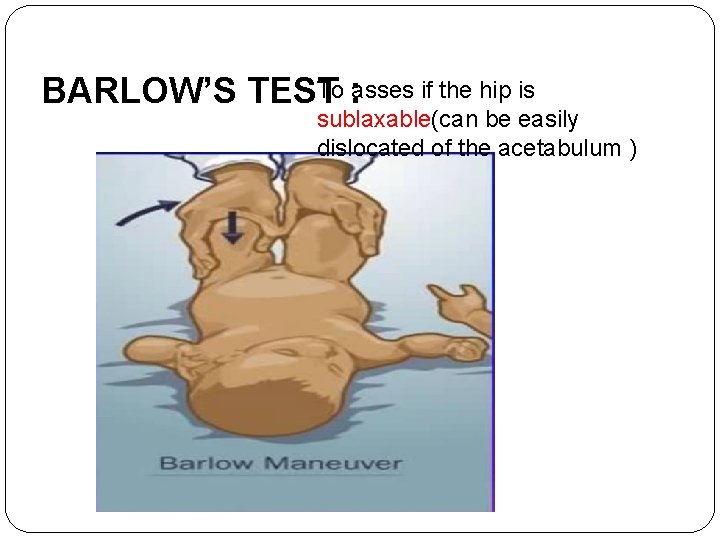

HOW TO ASSES HIP STABILITY IN INFANTS: � 1. Barlow test : a maneuver that is performed by adducting the hip while applying light pressure on the knee, directing the force posteriorly. If the hip dislocates (pops out of socket with a „clunk‟ is felt), the test is considered positive. The test is harmful and shouldn’t be done. � 2. Ortolani test : relocates the dislocation of the hip joint that has just been elicited by the Barlow maneuver by abducting the hip joint. � Barlow and Ortolani tests are inapplicable after 3 months of age because of certain changes that happen in the hip joint and make it fixed and no more reducible by that age. Specifically, this tests for posterior dislocation of the hip.

To asses if the hip is BARLOW’S TEST : sublaxable(can be easily dislocated of the acetabulum )